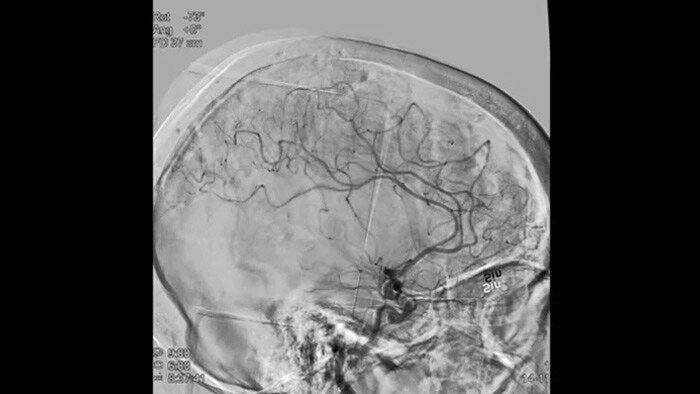

ClarityIQ aplica la compensación automática del movimiento durante la ASD en tiempo real para mantener imágenes nítidas de los vasos. Esto permite tomar decisiones con confianza durante los procedimientos para atender accidentes cerebrovasculares.

Visualización de la ASD

Las visualizaciones de la ASD de alta calidad le permiten evaluar si ha recuperado el coágulo completo y si los trozos de coágulo se han dispersado distalmente en el cerebro. Puede comprobar el restablecimiento del flujo sanguíneo en la penumbra y comprobar si hay hemorragias periprocedimiento.